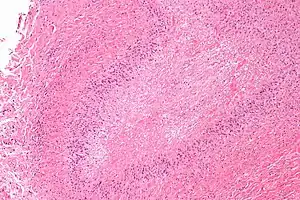

Micrograph of a rheumatoid nodule, showing the characteristic palisading granuloma with a core consisting of necrotic collagen and fibrin. H&E stain.

Histological examination of nodules shows that they consist of a shell of fibrous tissue surrounding a center of fibrinoid necrosis.[11] Pea-sized nodules have one center. Larger nodules tend to be multilocular, with many separate shells or with connections between the necrotic centers. Individual necrotic centers may contain a cleft or several centers of necrosis may all open on to a large bursal pocket containing synovial fluid.

The boundary between the necrotic center and the outer fibrous shell is made up of the characteristic feature of the nodule, which is known as a cellular palisade. The palisade is a densely packed layer of macrophages and fibroblasts which tend to be arranged radially, like the seeds of a kiwifruit or fig.[11] Further out into the fibrous shell there is a zone that contains T cells and plasma cells in association with blood vessels.[12] The histology of pulmonary nodules are similar to that of subcutaneous nodules, with central necrosis surrounded by palisading macrophages and inflammatory infiltrate.[5]